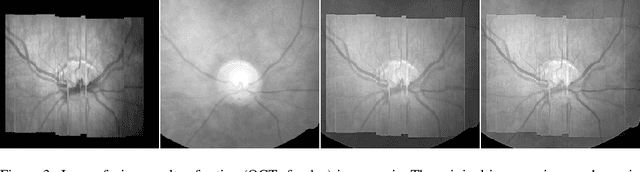

Abstract:The L1 norm regularized least squares method is often used for finding sparse approximate solutions and is widely used in 1-D signal restoration. Basis pursuit denoising (BPD) performs noise reduction in this way. However, the shortcoming of using L1 norm regularization is the underestimation of the true solution. Recently, a class of non-convex penalties have been proposed to improve this situation. This kind of penalty function is non-convex itself, but preserves the convexity property of the whole cost function. This approach has been confirmed to offer good performance in 1-D signal denoising. This paper demonstrates the aforementioned method to 2-D signals (images) and applies it to multisensor image fusion. The problem is posed as an inverse one and a corresponding cost function is judiciously designed to include two data attachment terms. The whole cost function is proved to be convex upon suitably choosing the non-convex penalty, so that the cost function minimization can be tackled by convex optimization approaches, which comprise simple computations. The performance of the proposed method is benchmarked against a number of state-of-the-art image fusion techniques and superior performance is demonstrated both visually and in terms of various assessment measures.